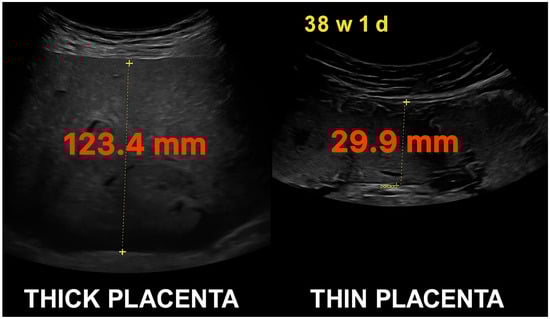

| Placental Thickness (PT) | The maximum perpendicular measurement of the placenta from top to bottom edge on ultrasound, excluding cord insertion. Reported in millimeters (mm). |